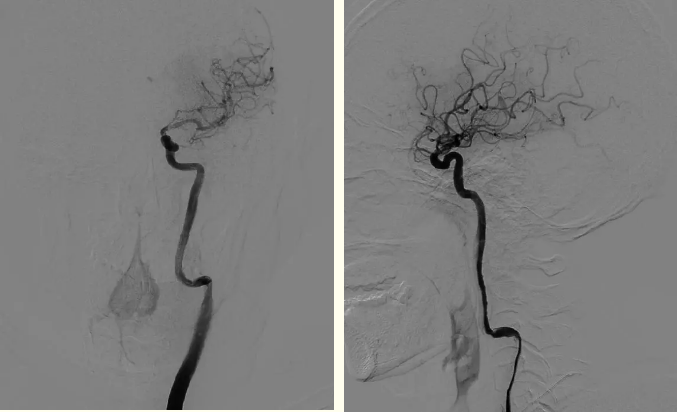

全脑血管造影显示患者左侧颈内动脉起始段闭塞,血栓负荷量大,手术难度较大,刘忠锦团队立即行机械取栓,经抽吸导管抽吸出大量血栓栓子,再给予支架取栓治疗,不断地努力后,终于打开了闭塞的大脑中动脉。造影显示右侧颈内动脉、大脑中动脉再通,观察10分钟后血流仍通畅,患者得救了,医护人员松了一口气。

术后血管再通影像